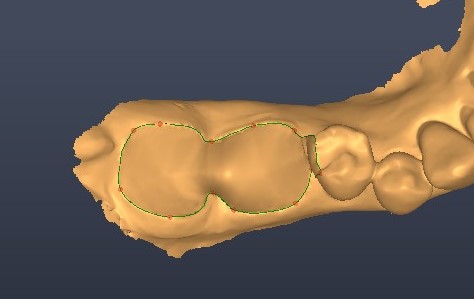

A guided surgical approach was selected, specifically a sleeveless guide, to make use of the precision that it affords in such cases. Dentiq software from 3DII (Dentiq Guide) was used to plan treatment, which allows for precise implant positioning. The surgical guide was then printed on a Phrozen Mini Sonic 8kS, ensuring high accuracy in execution.

Dental implants were then placed using the sleeveless surgical guides. The guided kit from CONELOG® is fantastic, as the screw-in carriers allow for very accurate positioning. After verifying the implant placement, the carriers are replaced and can be used to maintain patency of the implant opening while the graft material is packed into the site.